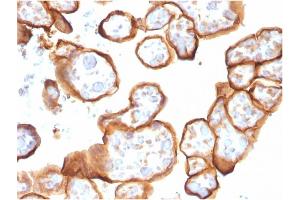

THBD 适用: 人 WB, IHC, ELISA, Coat, ISt, StM 宿主: 小鼠 Monoclonal THBD-1591 unconjugated

产品编号 ABIN6940727

100 μg (More quantities available)

发货至: 中国

获取报价